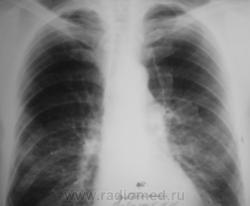

В связи с появившейся осиплостью голоса пациенту была проведена томография гортани.

3. Исследование.

На следующий день после томографии гортани была произведена томография верхушек.

4. Исследование.

Пациент был выписан под наблюдение онколога по месту жительства.

Ответы есть. Пациенту выставлена "четверка". Проведено шесть курсов "химии".

Все это было не в нашем ЛПУ - ЦРБ, а в областной туббольнице. Знаю только, что после биопсии диагноз был изменен, биопсия была также из лимфоузлов,  да и пациенту сильно похужело, сейчас уже не встает...